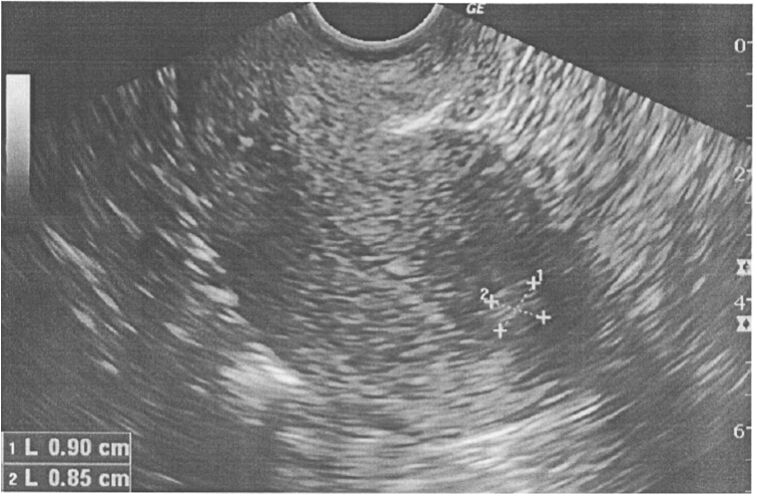

96 46 歲的女性育有一男一女,月經規則,大多 5 天結束,沒有量多或經痛的困擾;最近 2 個月發現月經 時間拉長為 8 至 10 天,而至婦產科求診,初步超音波檢查如附圖,下列何者判讀錯誤?(A)這是張腹部超音波 (B)這是張子宮矢狀切面(sagittal view) (C)標記處可能是子宮肌瘤 (D)標記處可能是內膜息肉